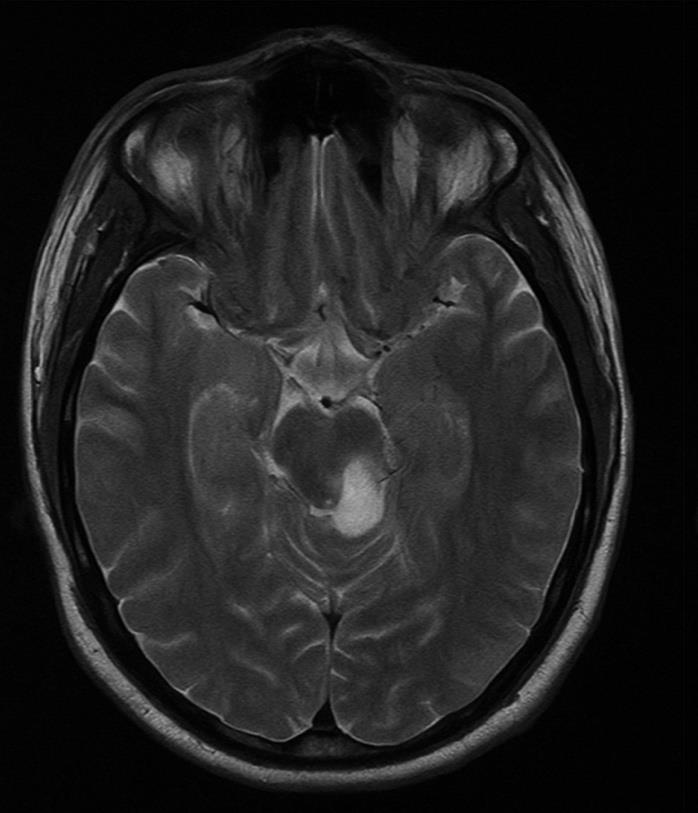

MRI of the brain and orbits (dated 11/06/2025) revealed a

subacute infarct involving both the dorsal and ventral aspects of the

right hemipons, extending inferiorly to the pontomedullary junction.

There was no susceptibility artifacts noted on SWI sequences, and no

abnormal enhancement was seen on post-contrast T1 images. Mild

cerebral atrophy was observed, with a global cortical atrophy (GCA)

score of 2.MR TOF angiography showed no significant vascular narrowing, aneurysms, or arteriovenous malformations in the intracranial circulation. The bilateral posterior communicating arteries were hypoplastic.

Figure 1:Impression: CEMRI study of the Brain with orbit reveals subacute

infarct involving dorsal and ventral right hemipons extending to the

pontomedullary junction. There is cerebral atrophic change (GCA score 2).